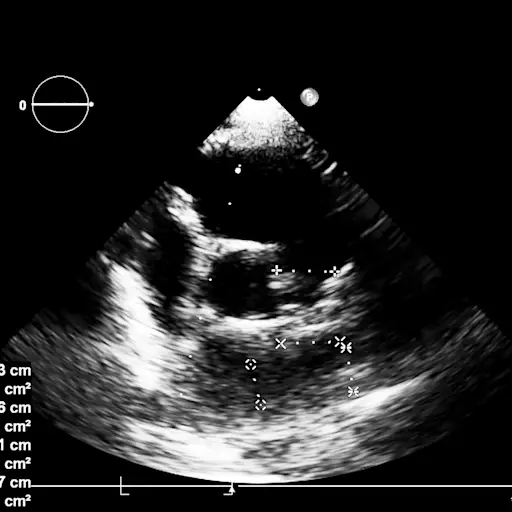

左阀泄漏

维韦克医生说,最常见的瓣膜疾病是二尖瓣返流.他解释说:“这是位于心脏左侧的二尖瓣没有完全闭合的地方。”这导致血液渗进左心房,而不是向前流进左心室。压力在肺部积聚,让你感到疲劳和呼吸急促。维韦克博士补充说:“随着时间的推移,这可能会导致心脏扩张或扩大,以及心脏功能障碍,泵本身由于泄漏而衰竭。”可能导致心力衰竭或心律失常(心律失常)。